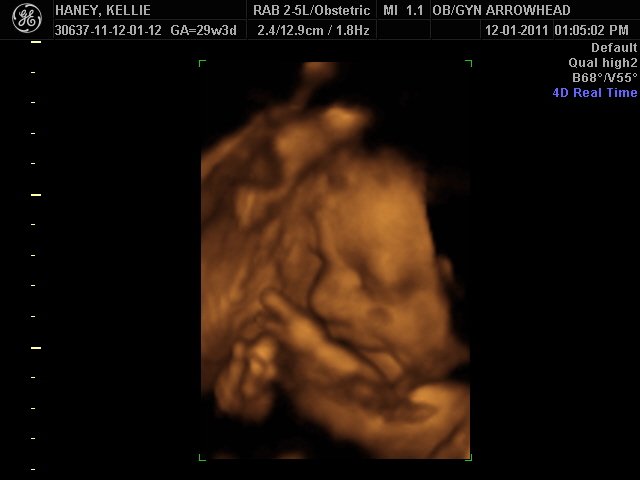

We offer complimentary 3D/4D Ultrasounds to all our OB patients around 30 weeks! The following photos are some examples of our work, shown with permission from our patients.